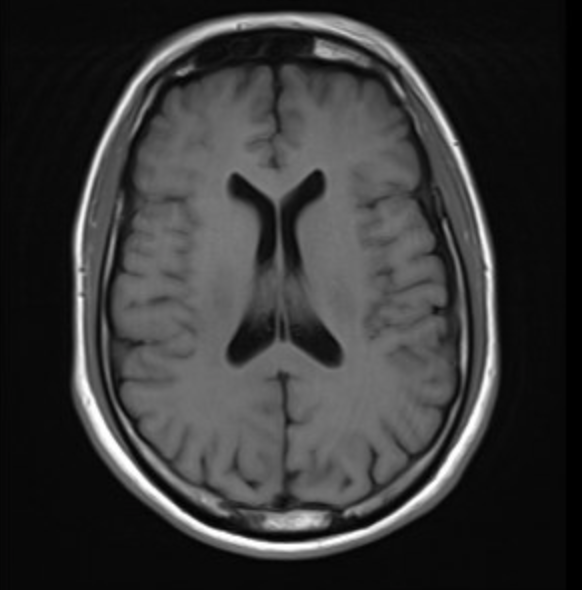

Case Presentation: A 43-year-old previously healthy male presented with acute onset mixed aphasia five days after recovering from an influenza A infection. He was last known well during a normal conversation with family before being found confused and unable to follow instructions at home. In the ED, initial CT and MRI brain imaging showed no acute ischemia, hemorrhage, midline shift, or herniation. Laboratory studies were notable for leukocytosis (WBC 13.34 × 10⁹/L), and urine drug screen was negative. On exam, he was alert and cooperative but exhibited severely impaired comprehension, repetition, naming, and reading, with preserved fluency. Lumbar puncture revealed an opening pressure with WBC 45 cells/µL (80% lymphocytes) and protein 68 mg/dL. CSF PCR was negative for HSV and VZV but positive for influenza A RNA, confirming the diagnosis of influenza-associated encephalitis. Additionally, his course was complicated by seizures in the right temporal lobe. He was treated with IV Peramivir, empiric acyclovir, and supportive care, then transitioned to oral Oseltamivir for a 10-day course. His symptoms resolved completely within five days, and follow-up MRI two weeks later showed near-complete resolution of temporal lobe lesions.

Discussion: IAE is a rare but serious complication of influenza infection, with most cases reported in pediatric populations. In adults, the condition is often underdiagnosed due to its nonspecific presentation. Pathogenesis involves both direct viral neuroinvasion and immune-mediated injury, leading to cerebral edema and encephalopathy. Diagnosis requires a high index of suspicion, especially in influenza season, and should include nasopharyngeal and CSF PCR testing, along with neuroimaging to differentiate IAE from other viral encephalitides such as HSV. Our case demonstrated classic findings, including bilateral temporal lobe hyperintensities on MRI and influenza A detection in CSF.Management strategies are largely supportive but should include early initiation of neuraminidase inhibitors, empiric antiviral coverage for alternative causes until ruled out, and intensive monitoring for complications such as seizures or cerebral edema. Prognosis is variable, with reported adult mortality rates between 10% and 30%. Our patient’s complete neurological recovery underscores the benefit of timely diagnosis and prompt antiviral therapy.